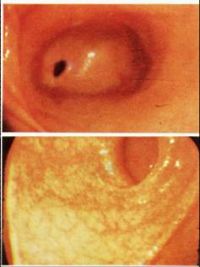

1.慢性浅表性胃炎又称慢性单纯性胃炎胃粘膜最常见的病变之一,国内胃镜检出率高达20%~40%,以胃窦部常见;胃镜见胃粘膜:胃粘膜充血、水肿,呈淡红色,可伴点状出血及糜烂,表面可有灰黄色或灰白色粘液渗出物覆盖;显微镜示:病变位于粘膜浅层;

2.慢性萎缩性胃炎根据发病是否与自身免疫有关及是否伴有恶性贫血,分为A、B型;A型属于自身免疫性疾病,患者抗壁细胞抗体(PCA)及抗内因子抗体(IFA)阳性,并伴有恶性贫血,病变主要位于胃体和胃底部;B型多见于胃窦部,无恶性贫血;两者胃粘膜改变相似;胃镜见胃粘膜:由正常的橘红色变为灰色或灰绿色,粘膜层变薄、皱襞变浅甚至消失、粘膜下血管透见,表面有细颗粒、偶见出血糜烂;显微镜可见淋巴细胞、浆细胞浸润、肠上皮化生、腺上皮化生、不典型增生;

胃镜检查是诊断胃炎的最好方法,胃镜检查能观察胃黏膜的改变,在进行胃镜检查的同时还可以钳取胃黏膜组织做组织切片,在显微镜下观察组织的病变情况,综合胃镜及病理检查结果确定诊断。